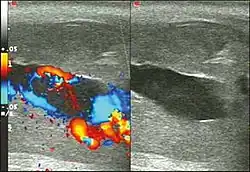

Blood gas testing the blood from the cavernosa of the penis can help in the diagnosis.[3] If the low-flow type of priapism is present, the blood typically has a low pH, while if the high-flow type is present, the pH is typically normal.[3] Color Doppler ultrasound may also help differentiate the two.[3] Testing a person to make sure they do not have a hemoglobinopathy may also be reasonable.[3]

Ultrasonography

Penile ultrasonography with Doppler is the imaging method of choice, because it is noninvasive, widely available, and highly sensitive. By means of this method, it is possible to diagnose priapism and differentiate between its low- and high-flow forms.[11]

In low-flow (ischemic) priapism the flow in the cavernous arteries is reduced or absent. As the condition progresses, there is an increase in echogenicity of the corpora cavernosa, attributed to tissue edema. Eventually, changes in the echotexture of the corpora cavernosa can be observed due to the fibrotic transformation generated by tissue anoxia.[11]

In high-flow priapism normal or increased, turbulent blood flow in the cavernous arteries is seen. The area surrounding the fistula presents a hypoechoic, irregular lesion in the cavernous tissue.[11]